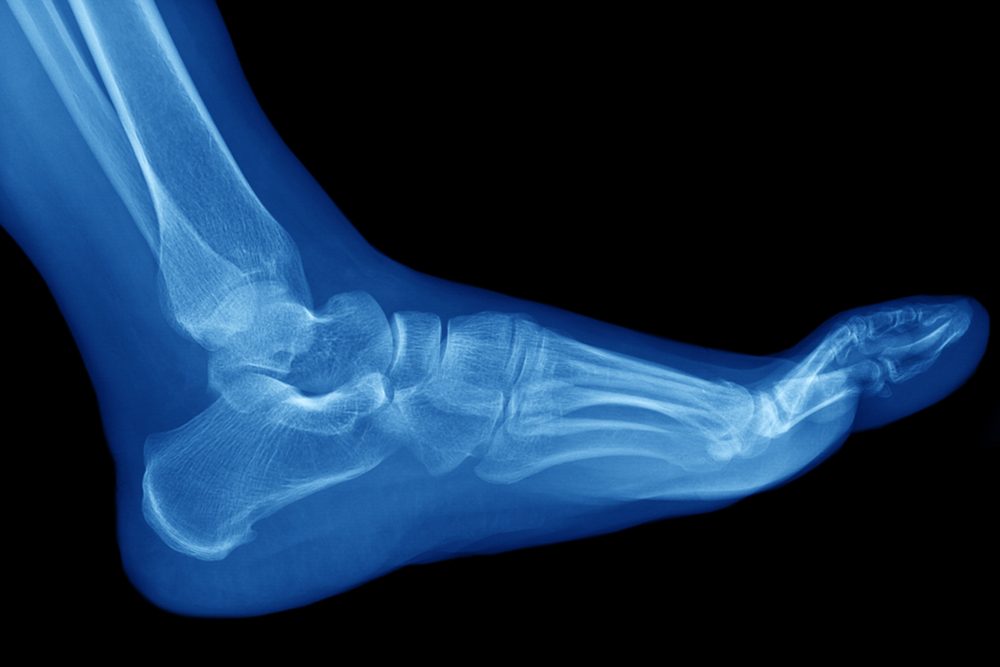

plantar fasciitis heel painIf you are experiencing pain on the bottom of your heel, there is a good chance that you may have a condition known as plantar fasciitis. Plantar fasciitis is an irritation and inflammation of the plantar fascia, which is a connective tissue that links the heel with the toes. Because the plantar fascia is located on the sole of the feet, it helps absorb the body’s weight, and can become overly stressed during walking, running, and jumping movements. Plantar fasciitis is the most common cause of heel pain and can make it difficult to walk. Common risk factors for plantar fasciitis include making certain repetitive movements (as in running) obesity, sudden weight gain (as in pregnancy), or by having flat feet or high arches or a tightened Achilles tendon. If you believe you have plantar fasciitis, make an appointment with a podiatrist to be properly diagnosed and to receive prompt and proper treatment.

feet 6The tibial nerve in the ankle enables movement and feeling in areas of the foot. When this nerve gets compressed, it forms what is known as tarsal tunnel syndrome.  This can happen as a result of a sprained ankle, or medical conditions that can include flat feet, high arches, or diabetes. Tarsal tunnel syndrome often causes severe pain and discomfort and is noticeable in the bottom of the foot and toes. Some of the tests that are performed to reach a diagnosis can include a nerve biopsy, and electromyography, which is a recording of electrical activity in the muscles. Treatment options can include resting and elevating the affected foot, and surgery may be recommended that can permanently reduce the pressure. Tarsal tunnel syndrome is diagnosed and treated by a podiatrist, and it is advised to consult with this type of doctor if you think you may have this condition.

foot boneFatigue fractures, which are known as stress fractures, occur when there is stress that is exerted on the bone. The foot is a common place for this to happen, and it can occur from increasing mileage and speed too quickly while running. The area may be tender to touch, and there can be severe pain and discomfort. A stress fracture can be confirmed when a proper diagnosis is performed. This can include having an X-ray or MRI taken, and then proper treatment can begin. It is beneficial to temporarily stop practicing the activity that led to the stress fracture. Patients have found mild relief when the affected foot is elevated. Many patients can perform non-impact exercises that can include swimming and cycling. This can help to maintain exercise goals while the injured foot is healing. Gradually, the normal routine of exercise and activities can be resumed, when the stress fracture has healed. If you feel you may have endured a stress fracture in your foot, it is strongly advised that you consult a podiatrist who can properly treat this condition.